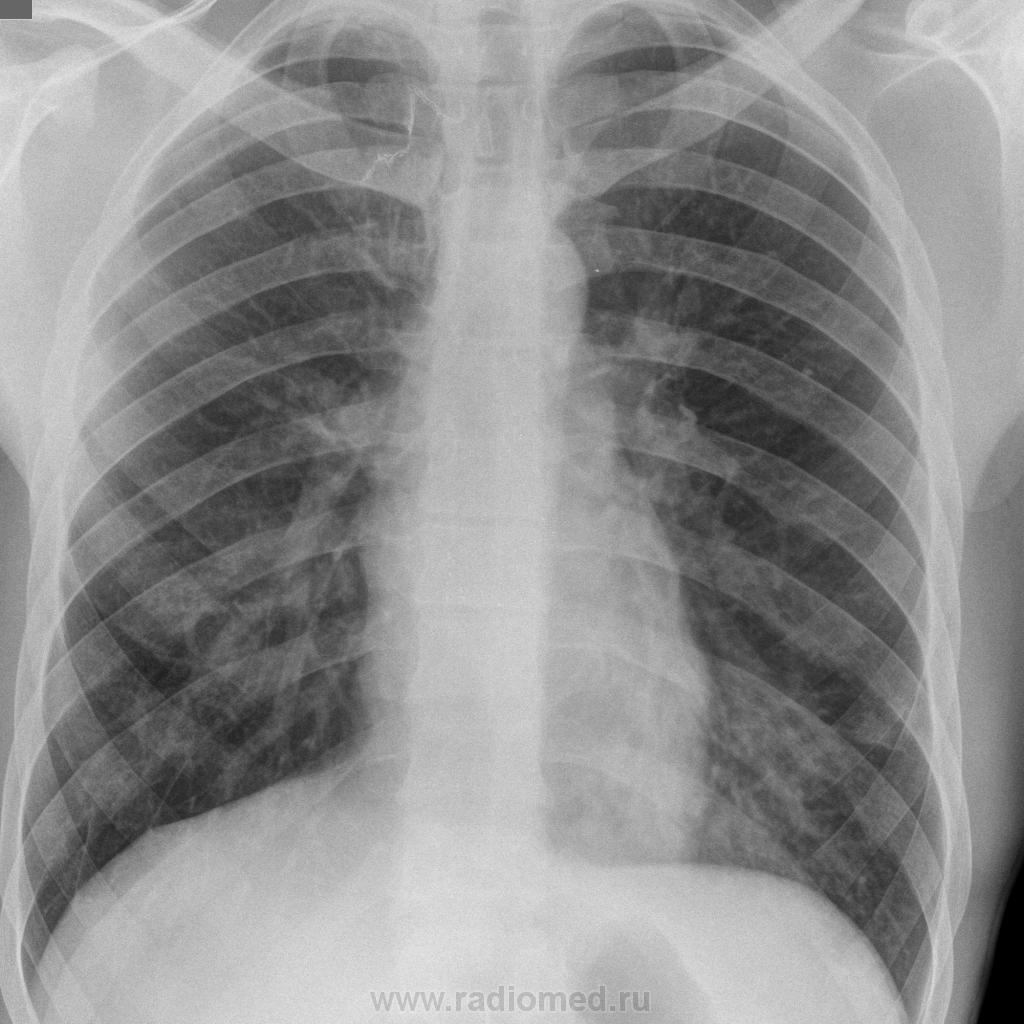

Мужчина, 24 г. Пришел на ФЛГ с жалобами на  кашель со скудной мокротой, повышение температуры до 38,5 С в течение 5 дней

В анамнезе - в 2009 будучи в армии болел TBC, оперирован, удалены S1,2 справа. Сразу оговорюсь - сделать линейные томограммы нет возможности.

Расценила изменения слева как пневмонические, но очень опасаюсь проглядеть tbc.

оперированного по поводу туберкулеза легких, появление бронхолегочных  признаков заставляет всегда думать о рецидиве заболевания. Это правильно. В данном случае имеет место пневмония.  Рекомендуйте исследование мокроты на МБТ №3. После лечения пневмонии представьте на сайт контрольные снимки. С уважением Nikolas

Коллеги, объясните что за тень на фоне позвонка на прицельном снимке?